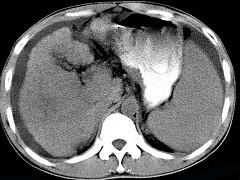

问题 男,35岁,有乙肝病史多年,AFP阳性,影像检查如图,最可能的诊断是 ( )

选项 A.肝硬化腹水 B.肝血管 C.肝脓肿 D.肝癌、硬化腹水 E.肝硬化,结节性增生

答案 D